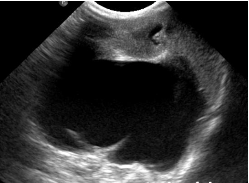

DX? (reins)

A

énorme structure anéchogène => bassinet extrêmement dilaté de liquide => hydronéphrose (obstruction urétérale)